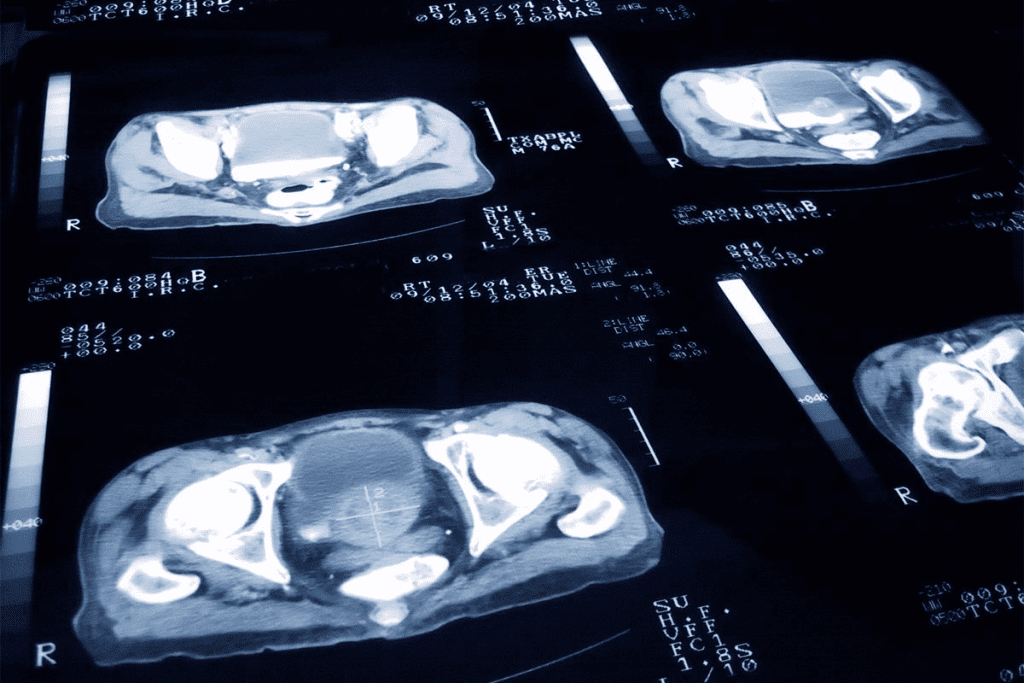

Urologists use advanced imaging, such as MRI, to find and manage prostate cancer. The prostate MRI procedure provides clear pictures of soft tissues without using harmful radiation, aiding accurate diagnosis and treatment planning.

We use MRI to see how far prostate cancer has spread and to find other issues. This safe test helps doctors make accurate diagnoses and treatment plans.

MRI is now a key tool in fighting prostate cancer. We use advanced MRI methods to spot cancer more accurately. This helps us make better treatment plans.

MRI technology has changed how we diagnose prostate cancer. It makes diagnosis more accurate and safer for patients. MRI has become a key part of diagnosing prostate cancer.